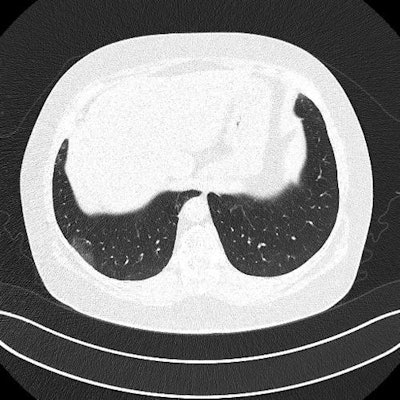

The three patients in the study, which was published in the Journal of Ultrasound in Medicine, had mild cases of COVID-19 but lingering shortness of breath. Ultrasound scans revealed a variety of pulmonary findings, including irregular pleural lines and B-lines, which correlated with abnormalities on CT scans.

- The 35-year-old woman had a mild, irregular pleural line and B-lines in her right anterior chest on ultrasound, which correlated with ground-glass opacities on CT.

- The 41-year-old woman had an irregular pleural line in her right lateral area on ultrasound, which correlated with pleural thickening on CT.

- The 64-year-old man had a marked, irregular pleural line and multiple B-lines on ultrasound, which correlated with fibrotic changes on CT.

The cases also beg the question of the best imaging modality for long-term follow-up of patients with persistent COVID-19 symptoms. While chest radiography and CT scans are being used as first-line modalities for symptomatic patients, the authors questioned their appropriateness for patients who may need long-term repeat imaging.